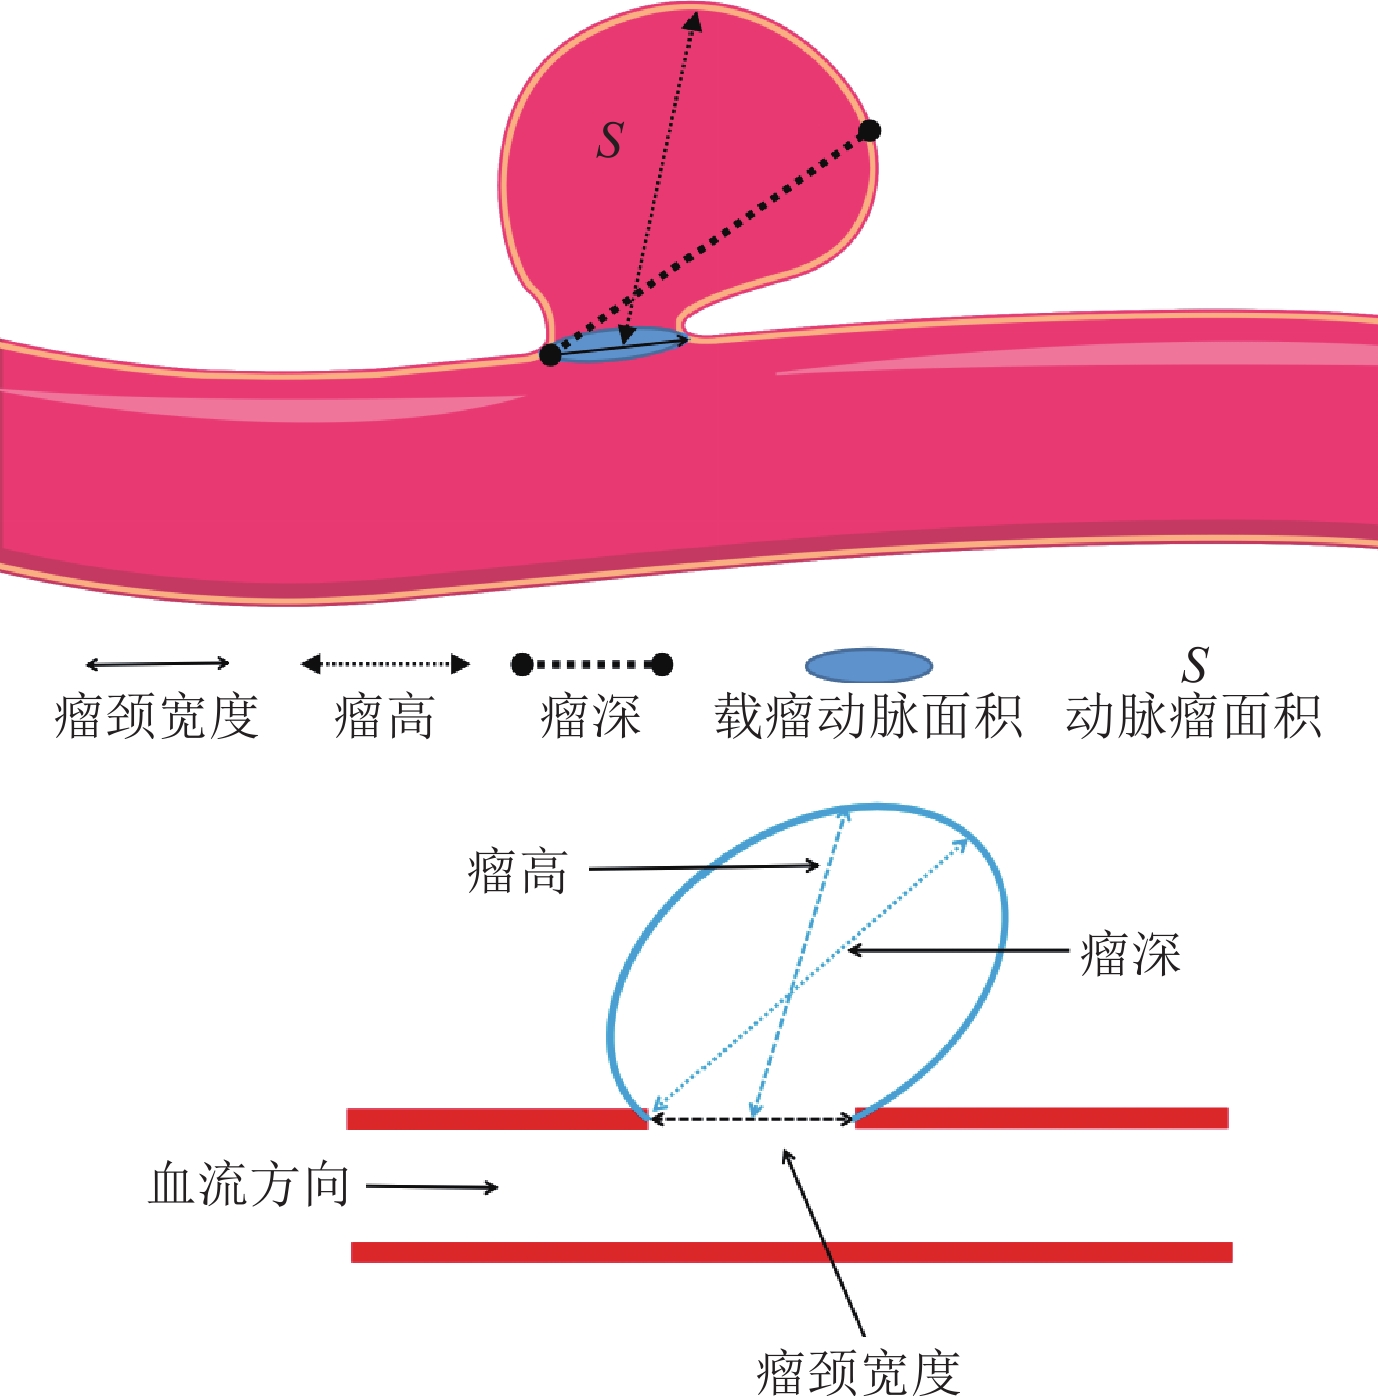

目的:探讨CT血管造影(CTA)在颅内动脉瘤破裂风险评估中的应用价值及形态学特征。方法:选取2018年10月至2021年10月蚌埠医学院第三附属医院颅内动脉瘤患者82例,所有研究对象均通过西门子64排128层螺旋CT及西门子数字减影血管造影(DSA)机实施CTA检查及DSA检查。统计分析本组患者瘤体破裂情况、不同瘤体破裂情况者形态学特征,并分析颅内动脉瘤瘤体破裂影响因素。结果:本组82例颈动脉患者瘤体破裂率为74.39%(61/82)、瘤体未破裂率为25.61%(21/82);瘤体破裂者子囊数目(60.66%)、面积比、SR、AR、瘤体长度大于瘤体未破裂者,瘤体破裂者动脉瘤单发情况(91.80%)、动脉瘤分布位置与瘤体未破裂者比较无显著差异。Logistic回归分析证实,面积比、SR、AR、瘤体长度均是导致颅内动脉瘤瘤体破裂的重要危险因素。结论:通过CTA检查可明确颅内动脉瘤患者瘤体形态学特征,评估瘤体破裂风险。

Abstract:Objective: To explore the application value and morphological characteristics of CT angiography (CTA) in the risk assessment of intracranial aneurysm rupture. Method: We included 82 patients with intracranial aneurysms from the Third Affiliated Hospital of Bengbu Medical College from October 2018 to October 2021. All study participants underwent CTA and digital subtraction angiography (DSA) examinations using Siemens 64 row 128 slice spiral CT and Siemens DSA machines. Statistical analyses were conducted on the condition of tumor rupture. The morphological characteristics of different tumor rupture cases, and the factors influencing intracranial aneurysm rupture were analyzed. Result: The rupture rate of 82 carotid artery patients in this group was 74.39% (61/82), and the non-rupture rate of the tumor was 25.61% (21/82). The number of sub-capsules (60.66%), area ratio, Size ration (SR), Aspect ratio (AR) and length of the ruptured aneurysm were greater than that of the unruptured aneurysm. The ruptured and unruptured aneurysms did not differ significantly in the incidence of single aneurysm (91.80%) and the distribution of aneurysms. Logistic regression analysis confirmed that area ratio, SR, AR, and tumor length were important risk factors for intracranial aneurysm rupture. Conclusion: CTA examination can clarify the morphological characteristics of intracranial aneurysms and evaluate the risk of tumor rupture.

形态学特征 组别 统计检验 瘤体破裂 瘤体未破裂 $\chi^2/t $ P 例数 61 21 - - 子囊数目n/% 37(60.66) 5(23.81) 8.489 0.004 面积比 2.98±0.84 1.89±0.56 5.527 <0.001 SR 2.31±0.86 1.59±0.64 3.511 0.001 AR 1.71±0.72 1.30±0.59 2.349 0.021 瘤体长度/mm 6.11±2.13 4.49±1.64 3.172 0.002 动脉瘤单发n/% 56(91.80) 20(95.24) 0.272 0.602 动脉瘤分布位置n/% 大脑前动脉 7(11.48) 5(23.81) 1.902 0.168 大脑中动脉 12(19.67) 4(19.05) 0.004 0.950 前交通动脉 15(24.59) 3(14.29) 0.968 0.325 后交通动脉 20(32.79) 3(14.29) 2.650 0.104 后循环 7(11.48) 6(28.57) 3.423 0.064 表 2 颅内动脉瘤瘤体破裂影响因素分析